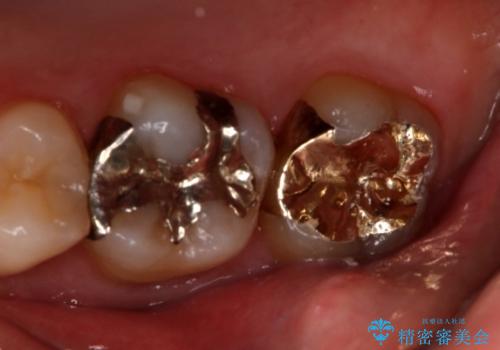

- 右上大臼歯の再治療を希望され来院された患者様です。

切削量と形状を考慮し、インレーでの治療を計画しました。

患者様がゴールドを希望されたのでゴールドインレーを選択しました。

ゴールドは金属の中でも硬すぎず破折すこともほとんどないため歯科の治療に適した材料と言われています。